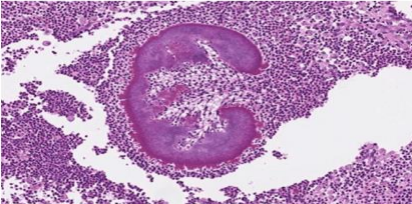

Notably, sulphur granules with actinomycotic colonies, filaments and club shaped structure (Speldore-Hoeppli reaction) were identified along within the abscess cavity [Figure 8, 9, 10]. The previously identified myofibroblasts on biopsy were attributed to reactive fibroblasts surrounding the abscess. Immunohistochemistry showed positivity for Ki-67 in 29.1% of cells and a few scattered IgG4-positive cells. ALK (5A4) and MUC-4 stains were negative.

FIGURE 8: Histopathology Spindle cell proliferative lesion

FIGURE 9: Sulphur granule Sulphur granule (black arrow) shown is composed of masses of gram-positive bacteria with branching filaments and eosinophilic amorphous material with club shaped configuration surrounding the granule (Splendore-Hoeppli reaction).

FIGURE 10: Sulphur granule Magnified view of sulphur granule and Splendore- Hoeppli reaction